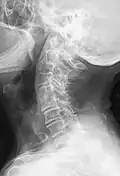

Blockwirbel an der Halswirbelsäule (HWK 4 und 5). Vom Bild her wohl auf der Basis degenerativer oder entzündlicher Veränderungen. -